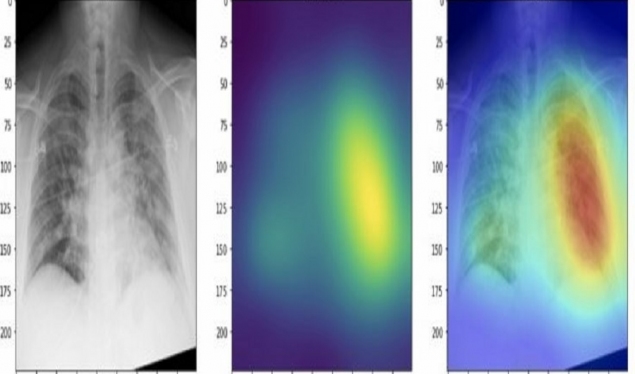

Mjeti i inteligjencës artificiale DeepCOVID-XR, i zhvilluar nga studiuesit nga Universiteti Northwestern në Ilinois të SHBA-së, mund të lexojë imazhe me rreze rëntgen në gjoks për të zbuluar COVID-19 më saktë dhe më shpejt se radiologët torakalë.

Sipas të dhënave të hulumtimit të botuara në revistën Radiology, mjeti u vu në provë dhe mund të zbulonte sëmundjen me saktësi 83 për qind, duke skanuar përmes 2,214 imazheve.